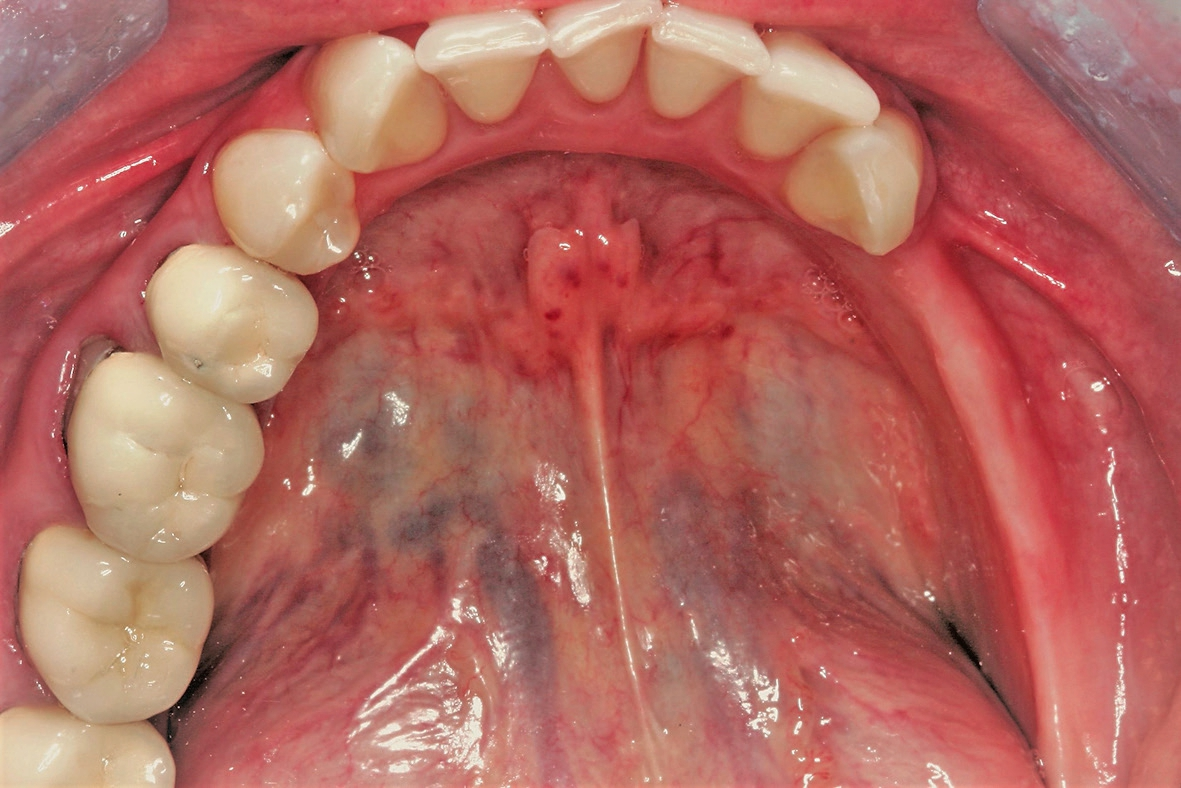

Eine 42 Jahre alte Frau stellte sich mit dem Wunsch nach einer festsitzenden prothetischen Versorgung im Unterkiefer vor. Die Voruntersuchung und die Röntgenaufnahmen zeigten eine Atrophie des Unterkiefers und damit ein für das Setzen von Implantaten eingeschränktes ortsständiges Knochenangebot (Abb. 1 und 2). Der Patientin wurden verschiedene Behandlungsoptionen für ein zweizeitiges GBR-Verfahren vorgestellt, um eine ausreichende Kammbreite für die anschließende Implantatbehandlung zu erhalten. Die Patientin lehnte ein Augmentationsverfahren mit autologem Knochentransplantat ab. Der vereinbarte Behandlungsplan beinhaltete letztendlich einen Knochenaufbau mit einem individuell konstruierten, gefriergetrockneten CADCAM-Allograft (maxgraft® bonebuilder, botiss biomaterials GmbH) und die anschließende Implantation von Straumann® BLX Roxolid® SLActive® Implantaten.